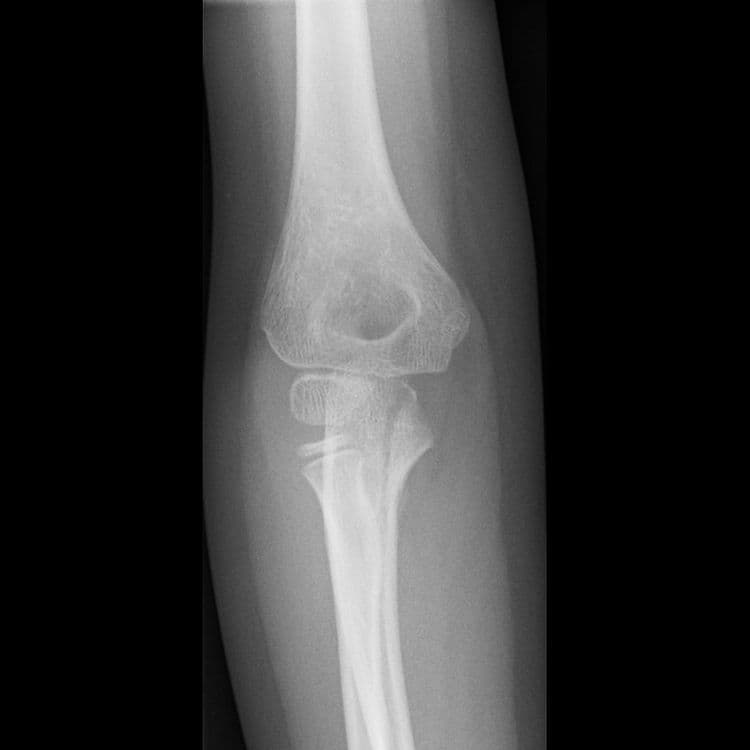

Impacted Fracture - एखादे हाड तुटते तेव्हा त्या हाडाचा हिस्सा दुसऱ्या हाडांमध्ये घुसण्याची स्थिती.

Fracture Dislocation - सांध्यातील एका हाडाला फ्रॅक्चर असल्याने सांधा निखळणे.